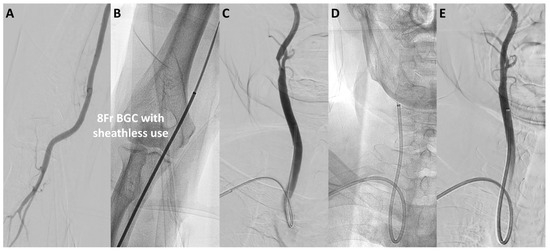

The median puncture size was reduced from 3.1 mm in the TFA-first period to 2.7 mm in the TRA-first period (p < 0.01; Figure 2B). Specifically, in the TFA-first period, the most commonly used devices were the 9Fr sheath BGC (40%) and the 6Fr guide sheath (GS) (48%). In the TRA-first period, however, the sheathless 8Fr BGC was widely used, accounting for 70% of cases, with minimal use of larger devices (p < 0.01). The widespread adoption of the sheathless 8Fr BGC during the TRA-first period was primarily due to its advantages in managing unstable plaque and providing enhanced support during device navigation. Representative cases of TRA CAS using the sheathless 8Fr BGC are illustrated in Figure 3 and Figure 4. Figure 3 shows a favorable anatomy case with smooth BGC navigation, while Figure 4 demonstrates a challenging anatomy case where BGC use was desired due to unstable plaque; however, balloon anchoring in the external carotid artery (ECA) was required to guide the BGC into position.

Figure 3. Representative case of TRA CAS using a sheathless 8Fr BGC in favorable approach anatomy. A representative case of CAS performed via the radial artery using a sheathless 8Fr BGC in favorable approach anatomy. (A,B) show the insertion of the 8Fr BGC (outer diameter 2.7 mm) into the radial artery using a sheathless approach (puncture size 2.7 mm). (C,D) demonstrate smooth navigation of the BGC into the right common carotid artery (CCA). (E) shows successful stent placement. Abbreviations: CAS, carotid artery stenting; CCA, common carotid artery; BGC, balloon guide catheter; TBA, transbrachial access; TRA, transradial access.